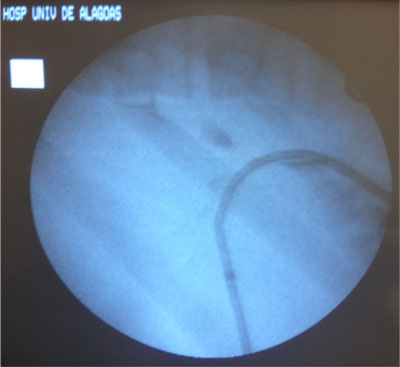

- Drenagem da Via Biliar e Dilatação da Estenose;

Dilatação com balão

- Balões maiores -> utilizados para a estenose do ducto biliar comum;

- Anastomoses biliares entéricas -> dilatação com um balão maior (10 a 20 mm de diâmetro);

Dilatação deve ser lenta e progressiva

- Evitar laceração do ducto biliar;

- Evitar sangramento no sistema biliar -> estenose fibrótica;